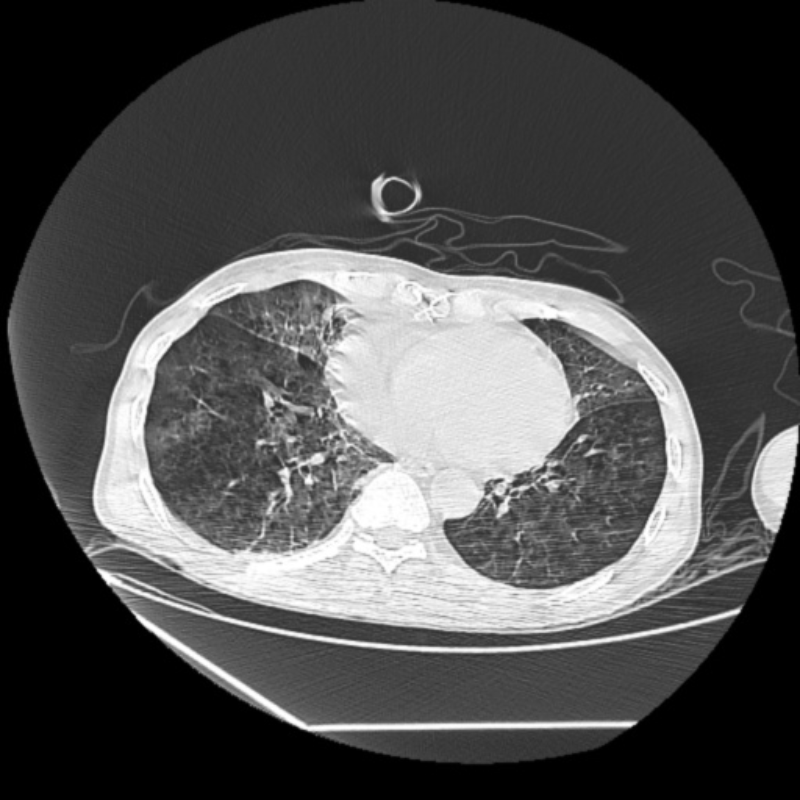

容伯伯到達急診醫(yī)學科急診搶救室后,還是神志昏迷、呼吸急促,心電監(jiān)測提示血氧飽和度低。急診搶救室吳文龍副主任醫(yī)師立即予以氣管插管接呼吸機輔助通氣治療,迅速完善血氣分析、CT等相關(guān)檢查后,擬“溺水”收入重癥醫(yī)學科。

文章配圖